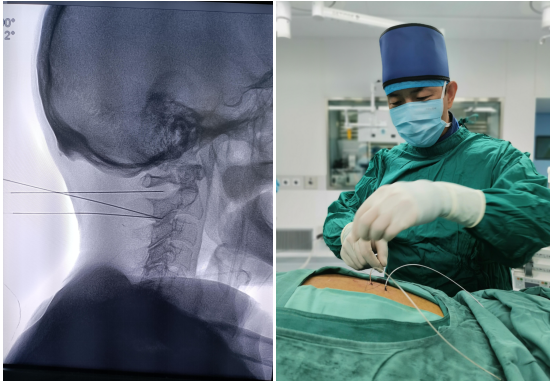

鞘内吗啡镇痛泵植入术(一)

鞘内吗啡镇痛泵植入术,又称“植入式鞘内药物输注系统”,是一种先进的微创介入镇痛技术。它通过将药物直接输送到脊髓周围的脑脊液中,像建立一个“直达疼痛中枢的精准给药通道”,从而高效地控制顽固性疼痛。它真正实现了 “用最小的药量,达到最强的效果,产生最少的副作用”的精准医疗目标,为众多深受顽固性疼痛折磨的患者提供了重返高质量生活的希望,是“舒适化医疗”理念的杰出体现。是目前国际上治疗顽固性疼痛及癌痛的核心技术。

鞘内吗啡本治疗示意图